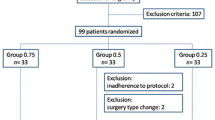

After providing their written informed consent, the patients were randomly assigned to receive an ultrasound-guided interscalene brachial plexus block (US-ISB) with one of three LA solutions. Sealed envelopes, prepared by an independent researcher who was never involved in the patient care during the study procedure, randomly allocated the participants to one of the three study groups: 0.5% LBup (0.5% levobupivacaine), 0.5% LBupEpi (0.5% levobupivacaine with 1/200,000 epinephrine), or 0.75% Rop (0.75% ropivacaine) (Fig. 1). The randomization technique for this study did not involve the use of stratification or blocks.

A total of 37 patients were randomized. Seven patients were excluded, including 4, due to pre-existing abnormal QST findings measured pre-procedure and 3, due to conversion from arthroscopy to open rotator cuff repair surgery. Thirty subjects completed the study without untoward reactions (Fig. 1: CONSORT Flow Diagram).